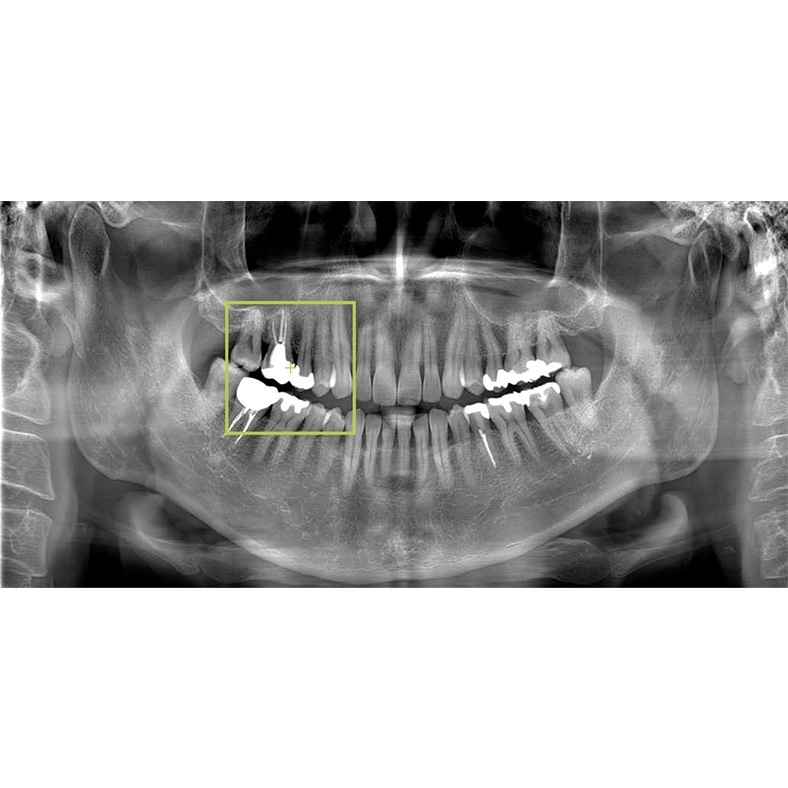

2 VERAVIEW (X800)_CP S(F40) M(R100) L(F150)

Information / DemoPanorama 3D - FOV Up bis zu: Ø 150 X H 140